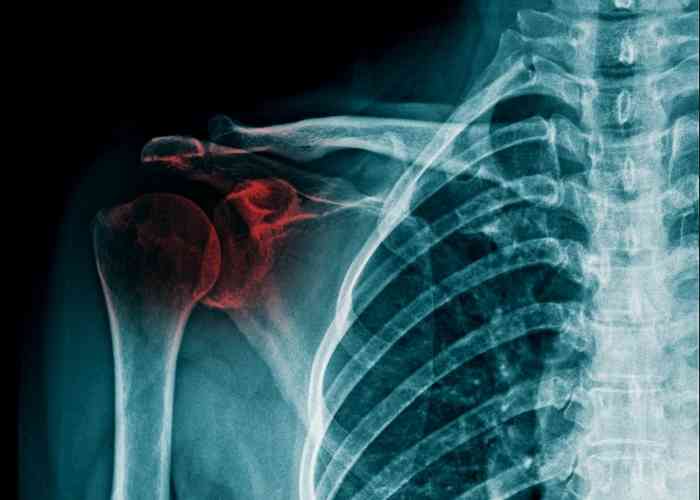

어깨뼈 골절의 입원 기간은 다양하며 상황에 따라 다를 수 있습니다. 일반적으로 어깨 골절의 경우 상완골 골절로 분류되며, 핀고정 수술이 필요한 경우 보통 1주에서 2주 정도의 입원 기간이 필요합니다. 그러나 교통사고나 다른 상황으로 어깨뼈 골절이 더 복잡한 경우에는 입원 기간이 더 길어질 수 있습니다. 따라서 개별 환자의 상태와 치료 방법에 따라 입원 기간이 결정됩니다.

어깨뼈 골절 수술 후, 입원 중에는 주로 진통제가 투여되어 통증을 관리합니다. 이로써 입원 중에는 통증이 그리 심하지 않게 느껴질 수 있습니다. 상완골 골절의 경우 핀고정 수술이 주로 시행되며, 수술 후에는 상완골의 고정이 유지됩니다.